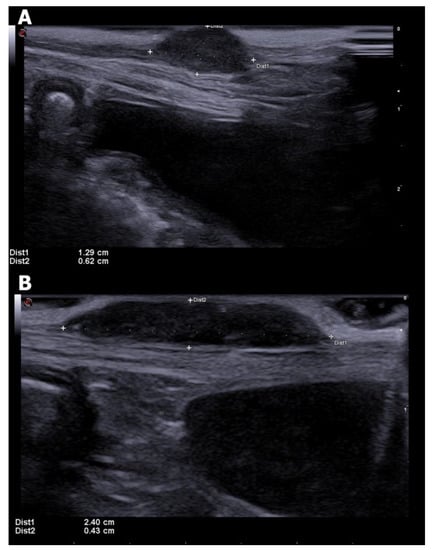

3.5. Regional Lymph Nodes

- Nyman, H.T.; O’Brien, R.T. The sonographic evaluation of lymph nodes. Clin. Tech. Small Anim. Pract. 2007, 22, 128–137. [Google Scholar] [CrossRef] [PubMed]

- Silva, P.; UScategui, R.A.R.; Maronezi, M.C.; Gasser, B.; Pavan, L.; Gatto, I.R.H.; Almeida, V.T.; Vicente, W.R.R.; Feliciano, M.A.R. Ultrasonography for lymph nodes metastasis identification in bitches with mammary neoplasms. Sci. Rep. 2018, 8, 17708. [Google Scholar] [CrossRef]

- Stan, F.; Gudea, A.; Damian, A.; Gal, A.F.; Papuc, I.; Pop, A.R.; Martonos, C. Ultrasonographic algorithm for the assessment of sentinel lymph nodes that drain the mammary carcinomas in female dogs. Animals 2020, 10, 2366. [Google Scholar] [CrossRef]

- Muramoto, C.; Sterman, F.A.; Hagen, S.C.F.; Pinto, A.C.B.C.F.; Oliveira, C.M.; Faustino, M.; Talib, M.S.F.; Torres, L.N. Ultrasonographic evaluation of lymphnodes for metastasis research of canine mammary tumor. Pesq. Vet. Bras. 2011, 31, 1006–1013. [Google Scholar] [CrossRef]